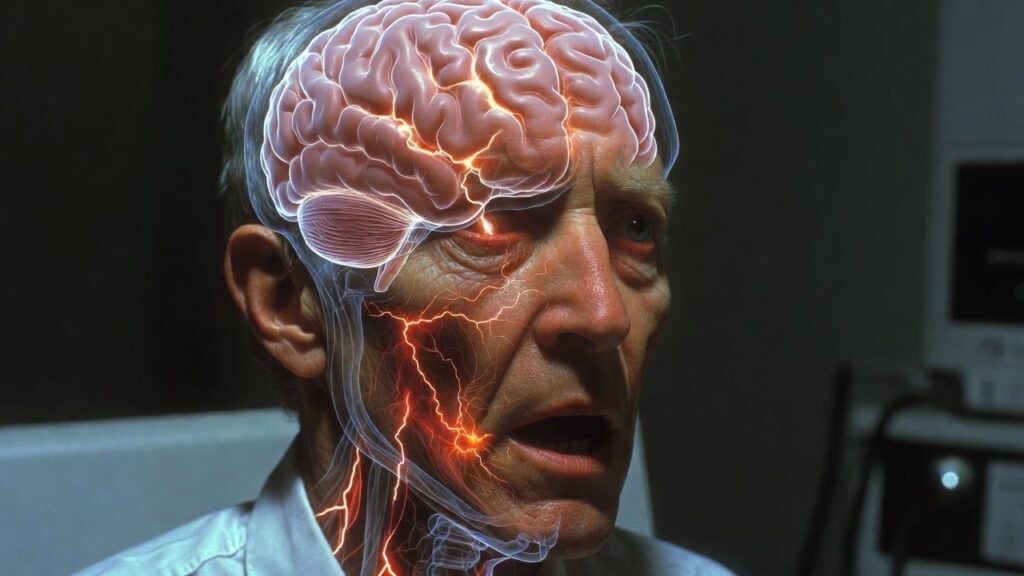

- Acute encephalitis

- Seizures

- Loss of consciousness

- Coma

Neuropsychiatric Manifestations

The Nipah virus is particularly troubling from a neurological and psychiatric point of view. In my clinical perspective, patients may exhibit:

• Acute delirium and confusion

• Behavior deprivation

• Anxiety and agitation

• Hallucinations

• Personality development

These symptoms emphasize the virus’s direct brain involvement and emphasize the need for multidisciplinary care.